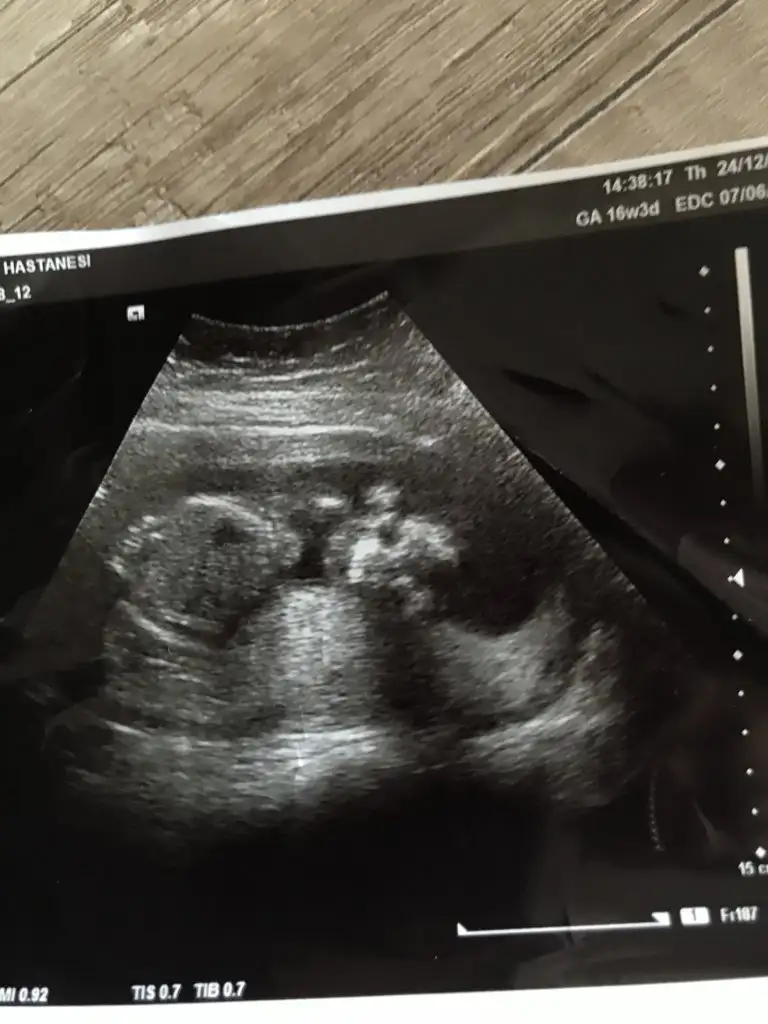

Karindan ise erkek vajinal ise kiz

Ayy çok teşekkürler. vajinaldiii. Kalp atışı çok fazla olduğu için doktor da kız olabilir dedi. Hadi bakalım